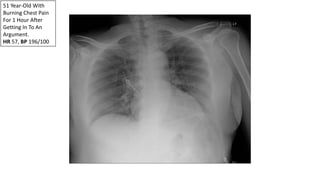

51 Year-Old With

Burning Chest Pain

For 1 Hour After

Getting In To An

Argument.

HR 57, BP 196/100

During His ED Stay

The Pain Migrates

To His Abdomen…

Aortic Dissection